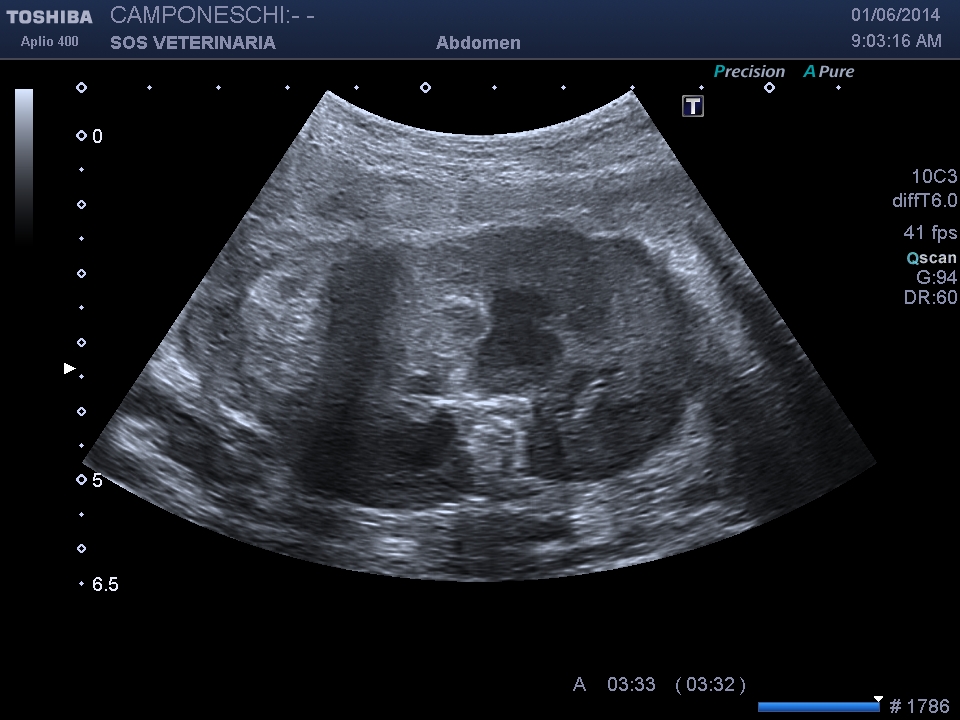

Beagle maschio 13 aa di nome Teo ,insorgenza iperacuta dopo trauma di lieve entita’ (caduta da un muretto alto meno di 1 metro) di sindrome algica addominale acuta ,l’esame ecografico mostra massa irregolare , disomogenea perirenale sx profilo d’organo irregolare e alterato con severa perdita di tessuto corticale ,quadro compatibile con grave infarcimento necrotico- emorragico , eseguito esame ceus ,ha confermato l’avascolarita’ della lesione ,in diagnosi differenziale e’ stato considerato emangiosarcoma renale con rottura secondaria al trauma .

milza lesione focale eterogenea

La minima entita’ del trauma ci ha fatto sospettare un emangiosarcoma allo stesso modo di quello splenico in pronto soccorso molto comune alla presentazione . dopo stabilizzazzione di 48 ore e’ stata eseguita nefrectomia .L’esame istopatologico ha escluso un emangiosarcoma e diagnosticato un grave e severo infarcimento necrotico-emorragico con distruzione del 30 % della massa renale ,si ipotizza la rottura di una anomalia presistente forse vascolare per la minima entita’ del trauma che non spiegherebbe se non come eccezione la gravita’ del quadro ..

Un’altra considerazione riguarda la Ceus che in questo caso non ha fornito altre indicazioni se non la conferma di una vasta lesione infartuale emorragica, forse in caso di emangiosarcoma, la presa del contrasto nella corteccia confinante sarebbe stata disomogenea e non netta la demarcazione tra tessuto sano e patologico ,le lesioni epatiche sono state prima dell’intervento campionate in citologia e nonostante fossero ipoenanchment in tutte le fasi sono risultate benigne di natura rigenerativa .